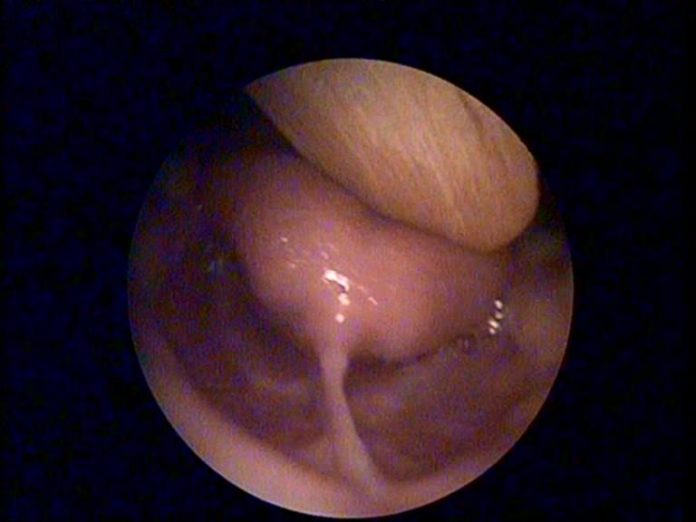

KBB - Kulak Burun BoğazDil BağıSağlık ve Hastalıklar Dil Bağı Nedir? Yazar Op. Dr. Atilla Şengör Share Facebook Twitter Google+ Pinterest WhatsApp Dil Bağı Nedir Bu videoda; Yenidoğanda dil bağı görülür mü? dil bağı kalınlığı … konularını izleyebilirsiniz.